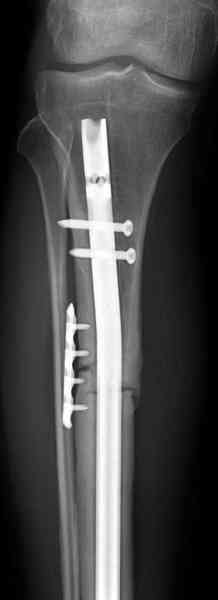

>Заполняли ли чем-нибудь пространство между кейджем и штифтом?

Нет. Просвет внутри кейджа - 13 мм, штифт - 12 мм. Не так там и много пространства то есть. Но вопрос правильный, интересный, из разряда современных нерешенных проблем.

Не оригинальное, подход не раз был демонстрирован нас в стране проф. Анатолием Федоровичем Лазаревым (ЦИТО), который это называет "металлокаркасная пластика". У нас в институте в другом отделении он

помогал сделать несколько таких металлокаркасов, только, насколько я помню, без блокируемых стержней. А в мире эта методика довольно давно

применяется, хотя и не массово. Например, осенью прошлого года на конференции общества Кюнчера в Страсбурге было хорошее сообщение на эту тему. 17 больных, результаты уже до 5 лет.

The cages are commercially available but up to 10 cm. So we measured the needed length on x-rays, added 2 cm at both ends for sure that

the resected piece will include all, and resulted with 15 cm which one was ordered and individually made by the same factory. So yes, we made the gap to fit the cage.

The inner diameter of the tube is 13 mm, the nail was 12 mm, so not so much space to put something inside. Yes, this is really shaft endoprosthesis which i hardly ever would offer for a young football player. Though... Maybe we would when we collect some experience with this sort of implants to feel/prognose its strength in different settings.